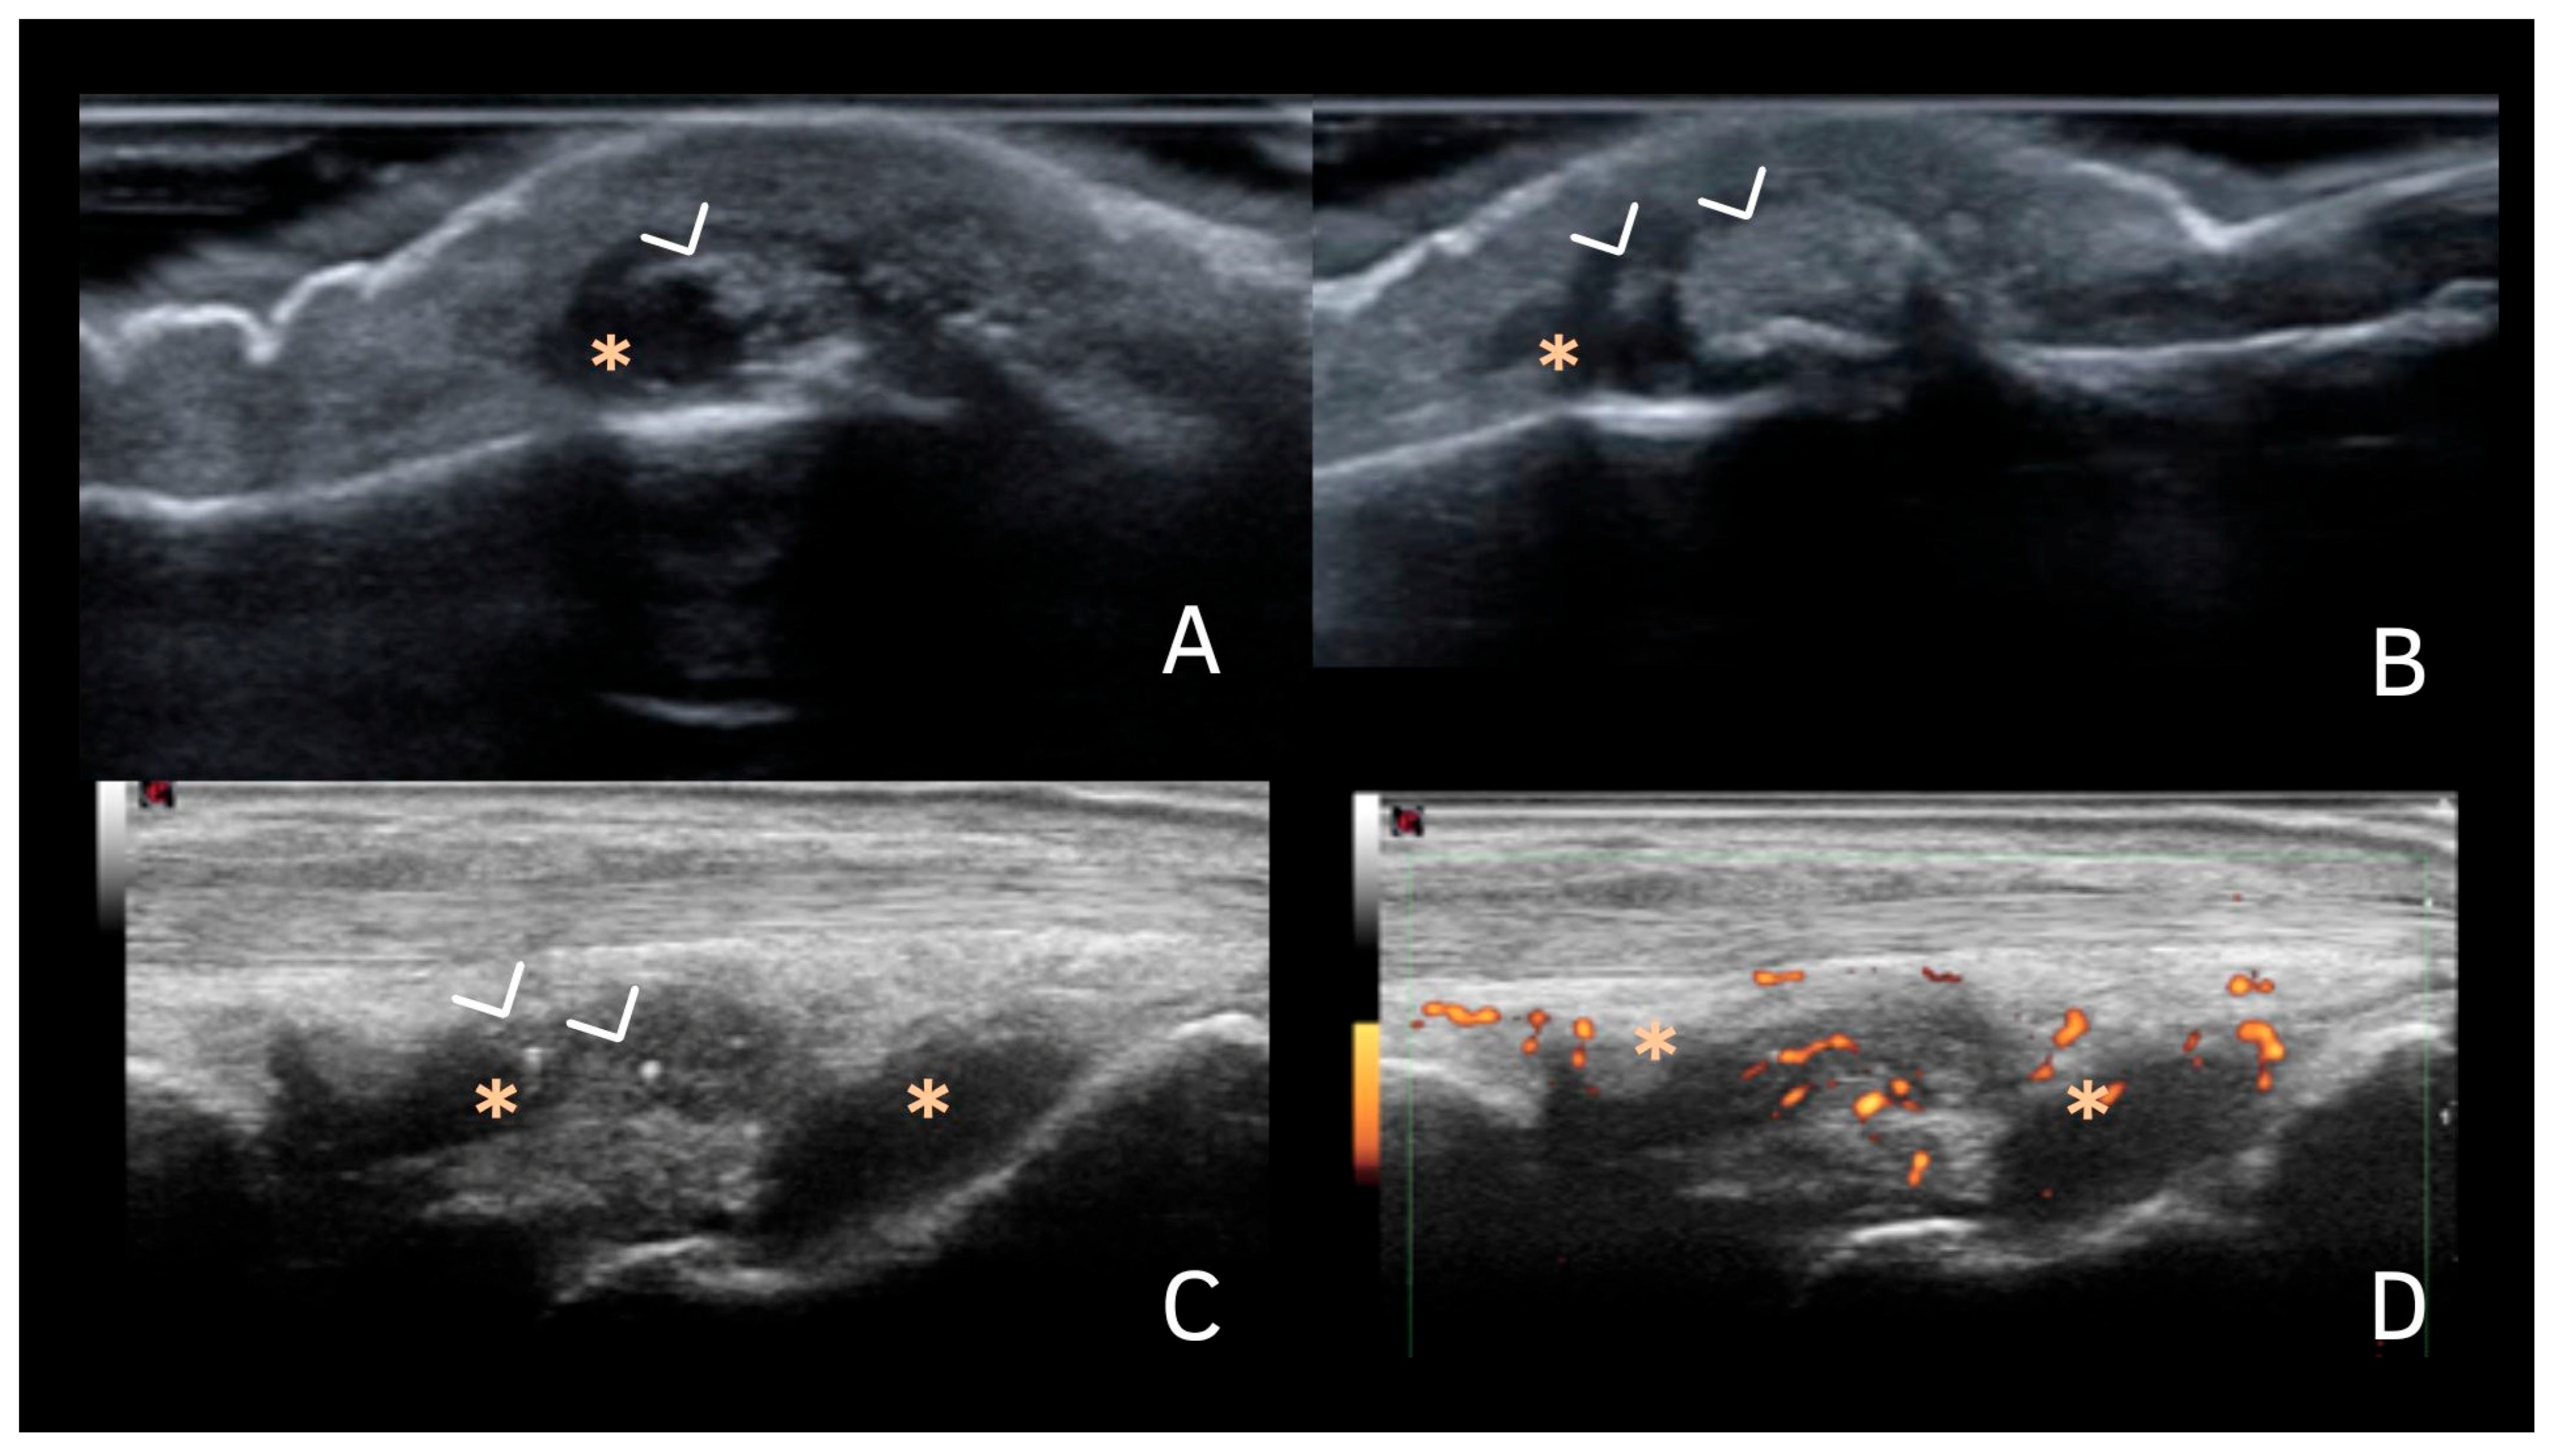

| Fibrocartilage | Shape: Deposits of variable shape. Echogenicity: Hyperechoic (similar to the bone cortex echogenicity). Localization: Within the fibrocartilage structure. Dynamic scanning: Remain fixed and move together with the fibrocartilage during dynamic assessment. Examples: Menisci, TFC, hip labrum, and acromioclavicular joint. |

| Synovial fluid | Shape: Deposits of variable shape and size. Echogenicity: Hyperechoic (similar to the bone cortex echogenicity), generally without posterior shadowing Localization: Within the synovial fluid. Dynamic scanning: Mobile according to joint movement and probe pressure. |